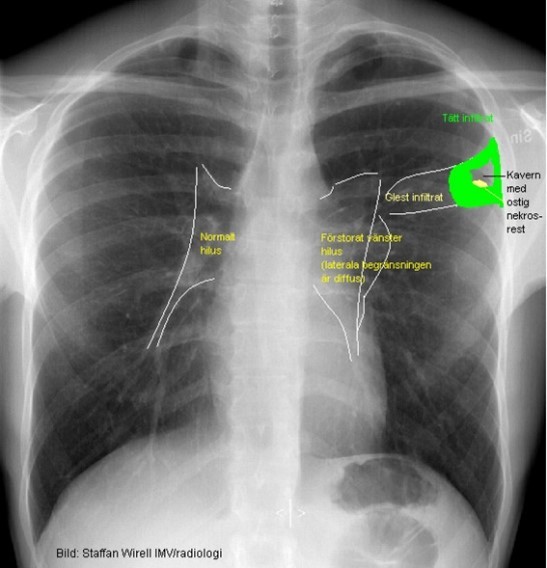

Lungröntgen av hostande patient:

Tuberkulos

Vad visar bilden?